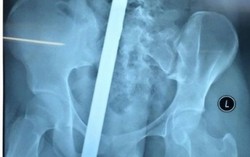

Va chạm với xe 3 bánh, nữ sinh bị thanh sắt đâm xuyên cơ thể

Chính trị - Xã hội 11:00 01/11/2016Trên đường đi học về, nữ sinh bị xe ba bánh chở vật liệu xây đựng đâm phải, khiến thanh sắt đâm xuyên từ mông đến thắt lưng.